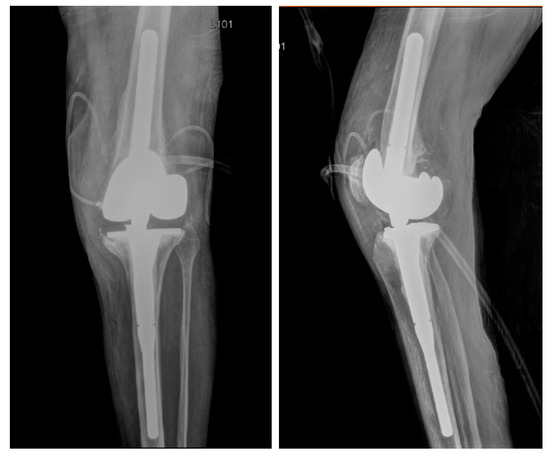

2. Case

3.4. DAIR Procedure and Bacteriophage Administration